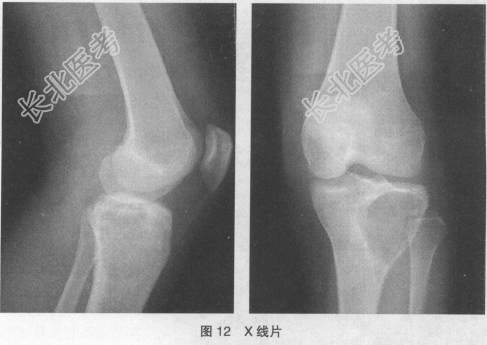

- [材料题] 患者,男性,36岁,1年前无明显原因出现左膝下隐痛,行走时加重,休息后可以缓解,夜间疼痛不明显,不需口服镇痛药。1个月前开始疼痛加重,并且左膝肿胀、活动受限。无体重减轻、恶病质等表现。无外伤史,无其他骨病、骨肿瘤病史和家族史,未予特殊诊断治疗。左膝下膨胀、皮温增高,可触及弹性骨壳(乒乓球)样肿块,有压痛,边界较清楚,无明显动度,左膝关节主动屈伸轻度受限,被动屈伸正常,全身浅表淋巴结无肿大。X线片检查结果如图12: